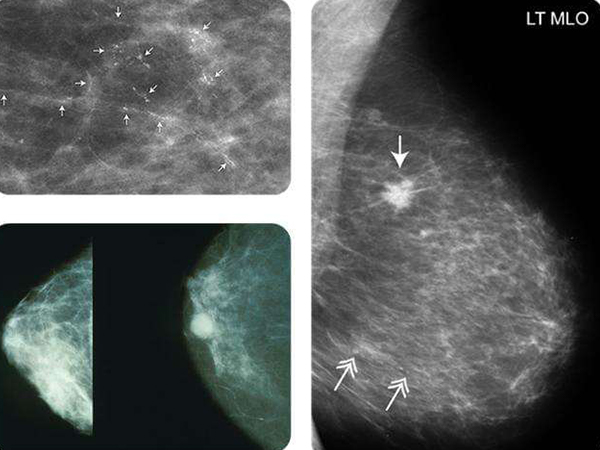

2、B超对微小钙化显示不清,钼靶具有特异性,钼靶可以诊断出彩超诊断不出来的结果,可以发现乳房内0.1mm以下的钙化处或钙化灶;

钼靶可以发现乳房0.1mm以下的钙化病灶

3、乳腺彩超检查可以观察乳腺病灶的基本物理特征,也可以观察乳腺病灶的血供情况,能比较立体地观察病灶位置,但乳腺钼靶检查在病灶钙化、密度高低等方面比较有优势;